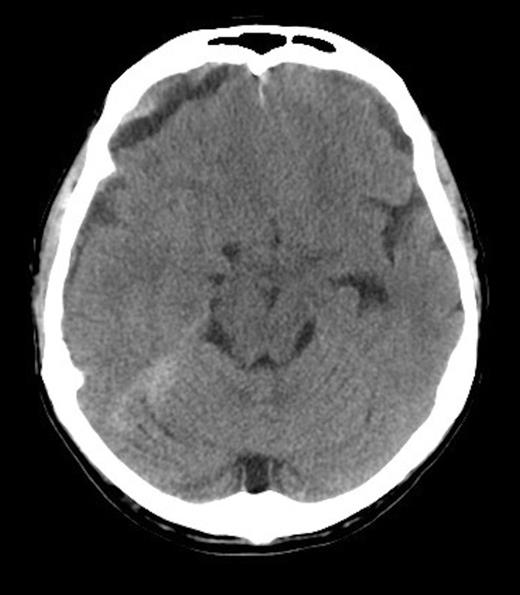

He received further platelet and plasma transfusion to correct his INR of 3.5, and was taken to theatre where a right parietal craniotomy and left parietal burrhole were performed to evacuate the SDH. Intraoperatively, the dura was noted to be thickened and subdural membrane tissue was obtained for histopathology. This was consistent with metastatic adenocarcinoma of the prostate (Figure 3 & 4). The patient recovered well day one post-operatively with no neurological deficits. His level of consciousness rapidly deteriorated on day two post-operatively, with no evidence of haematoma recurrence or neurosurgical complication on repeat CT Brain. The patient subsequently died on post-operative day four.

Histopathology Right subdural membranes: extensive infiltration by poorly differentiated adenocarcinoma cells with glandular infiltration (x10).